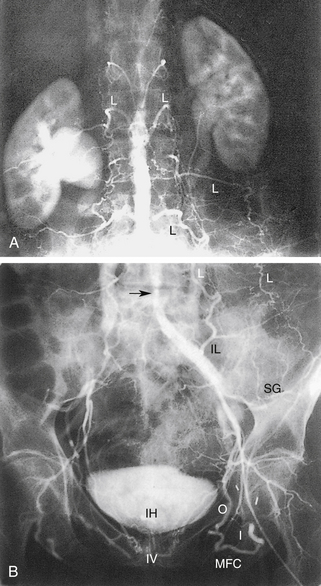

РИСУНОК 13-9. А. Брюшная аорта (Ао) заканчивается разветвлением на общие подвздошные артерии (CI) на уровне позвонка L4. Б. Общие подвздошные артерии делятся в пояснично-крестцовом соединении на внутреннюю (II) и наружную подвздошную (EI) артерии. Внутренняя подвздошная артерия (также называемая подчревной артерией) снабжает внутренние органы и мускулатуру таза. Ветви этой артерии становятся важными сопутствующими путями, как видно на других рисунках. Наружная подвздошная артерия переходит в общую бедренную артерию у паховой связки, как показано на рисунке 13-10 . C : Трехмерная объемная (VR) компьютерная томографическая (КТ) ангиограмма аорты и сегмента подвздошно-бедренной артерии. D. Проекция максимальной интенсивности (MIP) КТ-ангиограммы подвздошно-бедренных сегментов демонстрирует очаговые кальцификации в открытых сосудах. E — магнитно-резонансная ангиограмма (МРА) с усилением гадолинием аорты, подвздошного и бедренного сегментов. Анатомия наглядно иллюстрируется методами трехмерной реконструкции. С, чревная артерия; H, печеночная артерия; НМА, нижняя брыжеечная артерия; R, левая почечная артерия; рРГ – замена правой печеночной артерии; S, селезеночная артерия; СМА, верхняя брыжеечная артерия.

1. Обструкция дистального отдела аорты или двусторонней общей подвздошной артерии.а. Коллатеральный кровоток из артерий грудной и брюшной стенок в артерии таза, дистальные по отношению к обструкции.б. Коллатеральный кровоток из артерий кишечника в тазовые артерии, дистальные по отношению к обструкции.в. Коллатеральный кровоток из поясничных артерий в тазовые артерии, дистальнее места обструкции.

2. Односторонняя обструкция общей подвздошной артерии.а. Коллатеральный кровоток из контралатеральной подвздошной и/или бедренной артерий в артерии таза или бедра, дистальнее обструкции.б. Коллатеральные пути, как только что упоминалось, с кровоснабжением ипсилатеральных тазовых артерий.

3. Обструкция наружной подвздошной и общей бедренной артерии.а. Коллатерали, отходящие преимущественно от ипсилатеральных тазовых артерий или контралатеральных тазовых и/или бедренных артерий, кровоснабжающих артерии проксимального отдела бедра, дистальнее обструкции.б. Ранее упомянутые пути также, возможно, задействованы в различной степени.